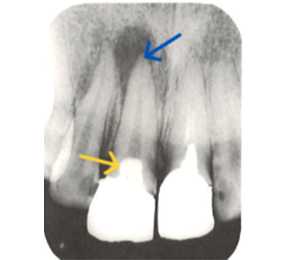

こちらのレントゲン写真を見てください。どちらかの歯医者さんで神経を取っています。根管に入れる薬は白く映ります。赤矢印部分です。一番右側が模式図ですが、青い部分が薬、根っこの先の赤点が化膿している部分です。

薬がほとんど入っていないのがわかります。黄矢印部分です。青矢印まで薬が入らないといけないのですが、全く入っていません。その結果、根っこの先が黒くなっています。膿が貯まって化膿すると黒く写ってくるのです。

別な歯科医院で治してもらいました。薬が根の先まで入っているのがわかります(黄矢印)。 根尖の黒い影が消失しています(赤矢印)。骨が再生すると白く写るようになります。

大事な話なのでもう一度説明します。

①の写真はどちらかの歯医者さんで神経を取ってもらったレントゲン写真です。根っこの中に薬が全く入っていません。

②の模式図で青く描かれている部分が薬です。

根の先を見ると小豆ぐらいの大きさの黒い影が見えます。根の中でばい菌が繫殖し感染を起こすとこのような黒い影ができます。黒い影の部分は膿(ウミ)が貯まっています。こうなると腫れて痛みが出てくるのです。

③、④の写真はそれを治した後のレントゲン写真とその模式図です。白く映っている薬が根の先まできちんと入っているのが確認できます。そして根の先にあった黒い影が消えているのが分かります。根の先の炎症が治って、骨が再生すると白く映るのです。

実はこのケース、歯医者さんの神経を取る治療でこのような根っこの病気になってしまったのです。そこでこの患者さんは神経を取った歯医者さんではなく、別の歯医者さんに受診して、根っこの治療をして治したのです。